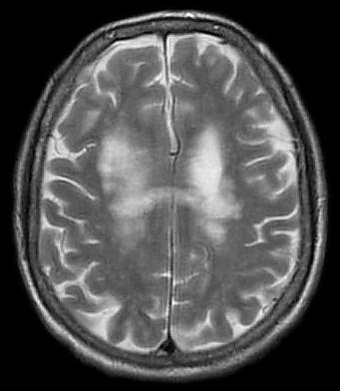

Магнитно-резонансная томография (МРТ) является по сравнению с компьютерной томографией предпочтительной методикой. В Т2-взвешенных изображениях определяются гиперинтенсивные очаги — асимметрично распределённые в белом веществе лобных и теменно-затылочных отделов, а также в корковом веществе, в стволе мозга и мозжечке, без захвата контрастного вещества или с незначительным захватом; увеличения объёма ткани не наблюдается. В Т1-взвешенных изображениях эти очаги гипоинтенсивны. У одной трети пациентов также обнаруживаются инфратенториальные очаги, которые могут также определяться изолированно[9].